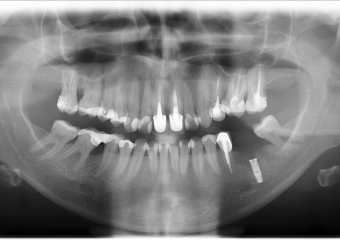

Raio X após instalação de um implante inferior

Raio X com prótese provisória fixa sobre o implante

Raio X final com prótese definitiva em porcelana instalada